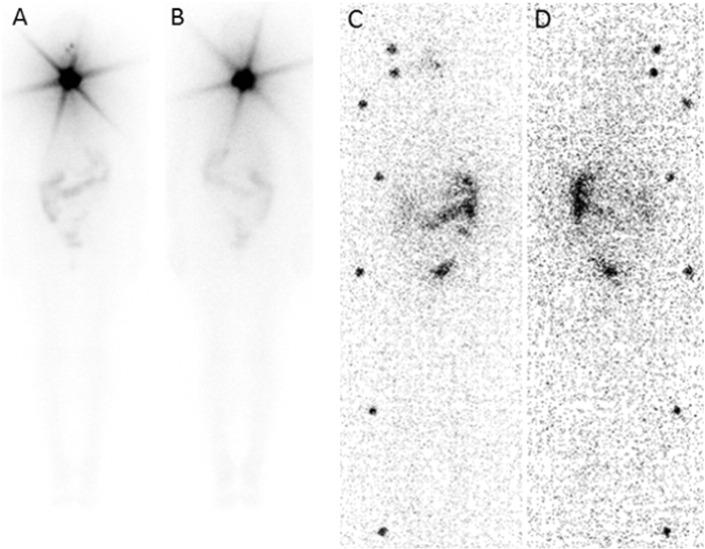

Malignant struma ovarii (SO) is a rare tumor, and as a consequence, treatments and follow-up procedures are not clearly established. Presented in this study are two cases of suspicious ovarian masses, resected and corresponding to malignant SO on histopathology. Similar to thyroid cancer, we proposed complementary radioiodine therapy ((131)I) after total thyroidectomy (no malignancy was observed at this level in our two patients). Patients underwent treatment with 3.7 GBq (131)I followed by post-therapy whole-body scintigraphy, which can detect residual disease or occult metastases. Thyroid remnant ablation increases the sensitivity and specificity of follow-up testing using serum thyroglobulin levels as a tumor marker. Our two patients remained disease-free for 3 and 5 years, respectively, after treatment.

恶性卵巢甲状腺肿(SO)是一种罕见肿瘤,因此,其治疗方法和随访程序尚未明确确立。本研究报告了两例可疑卵巢肿块病例,经切除后组织病理学检查确诊为恶性SO。与甲状腺癌相似,我们建议在全甲状腺切除术后进行辅助放射性碘治疗((131)I)(我们的两名患者在此水平未观察到恶性病变)。患者接受了3.7GBq(131)I治疗,随后进行治疗后全身闪烁扫描,该扫描可检测残留疾病或隐匿性转移。甲状腺残余组织消融可提高以血清甲状腺球蛋白水平作为肿瘤标志物的随访检测的敏感性和特异性。我们的两名患者在治疗后分别无病生存了3年和5年。